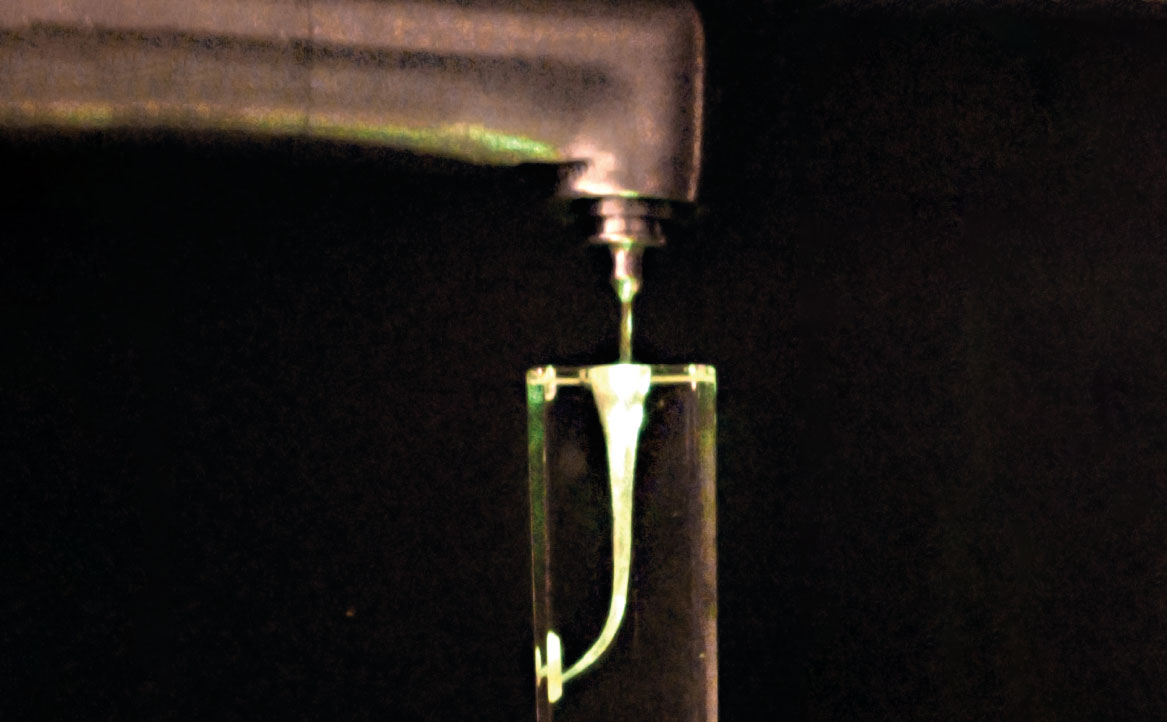

La tecnica di attivazione laser degli irriganti (LAI) si basa su effetti fotoacustici e fododinamici: il forte assorbimento del laser ad erbio da parte dell’acqua (o, nel caso di specie, degli irriganti) determina un fenomeno di vaporizzazione con la formazione di bolle di vapore, che implodono in 100-200 µs, scatenando così un effetto di cavitazione secondaria.

La specifica tip, che viene collocata all’interno della camera pulpare insieme all’irrigante (fig. 6), genera coppie di impulsi (ultra-short, 25µs) in grado di generare delle bolle: durante il collasso della bolla generata dalla prima irradiazione, viene emesso un secondo impulso in grado di generare una seconda bolla, che va a causare un ancor più rapido e violento collasso della prima. Il susseguirsi di questi collassi genera un’onda d’urto negli irriganti, capace di potenziare l’azione di disinfezione del canale (fig. 7). In altre parole, le bolle secondarie sono in grado di esercitare una pressione sulle prime tale da causare turbolenti moti degli irriganti in aree più profonde del sistema canalare, risultando così più efficaci della tecnica PIPS o delle tecniche di attivazione ad ultrasuoni in termini di eliminazione di detriti o smear layer, nonché in termini di capacità di penetrazione nei canali laterali (9).